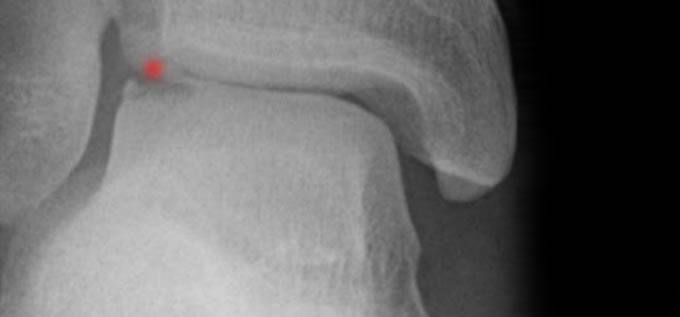

Las lesiones osteocondrales de tobillo afectan al grueso del cartílago y el hueso subcondral adyacente provocando alteraciones en la normal relación entre las superficies articulares existentes. Diferenciamos dos tipos principalmente: Osteocondritis disecante y fracturas osteocondrales.

La osteocondritis disecante es la fractura osteocondral de la cúpula del astrágalo. Se puede clasificar en cuatro etapas.

El diagnóstico de las lesiones osteocondrales se basa en la entrevista con el paciente, la exploración clínica y las pruebas de imagen: radiografia y TC o RM fundamentalmente.